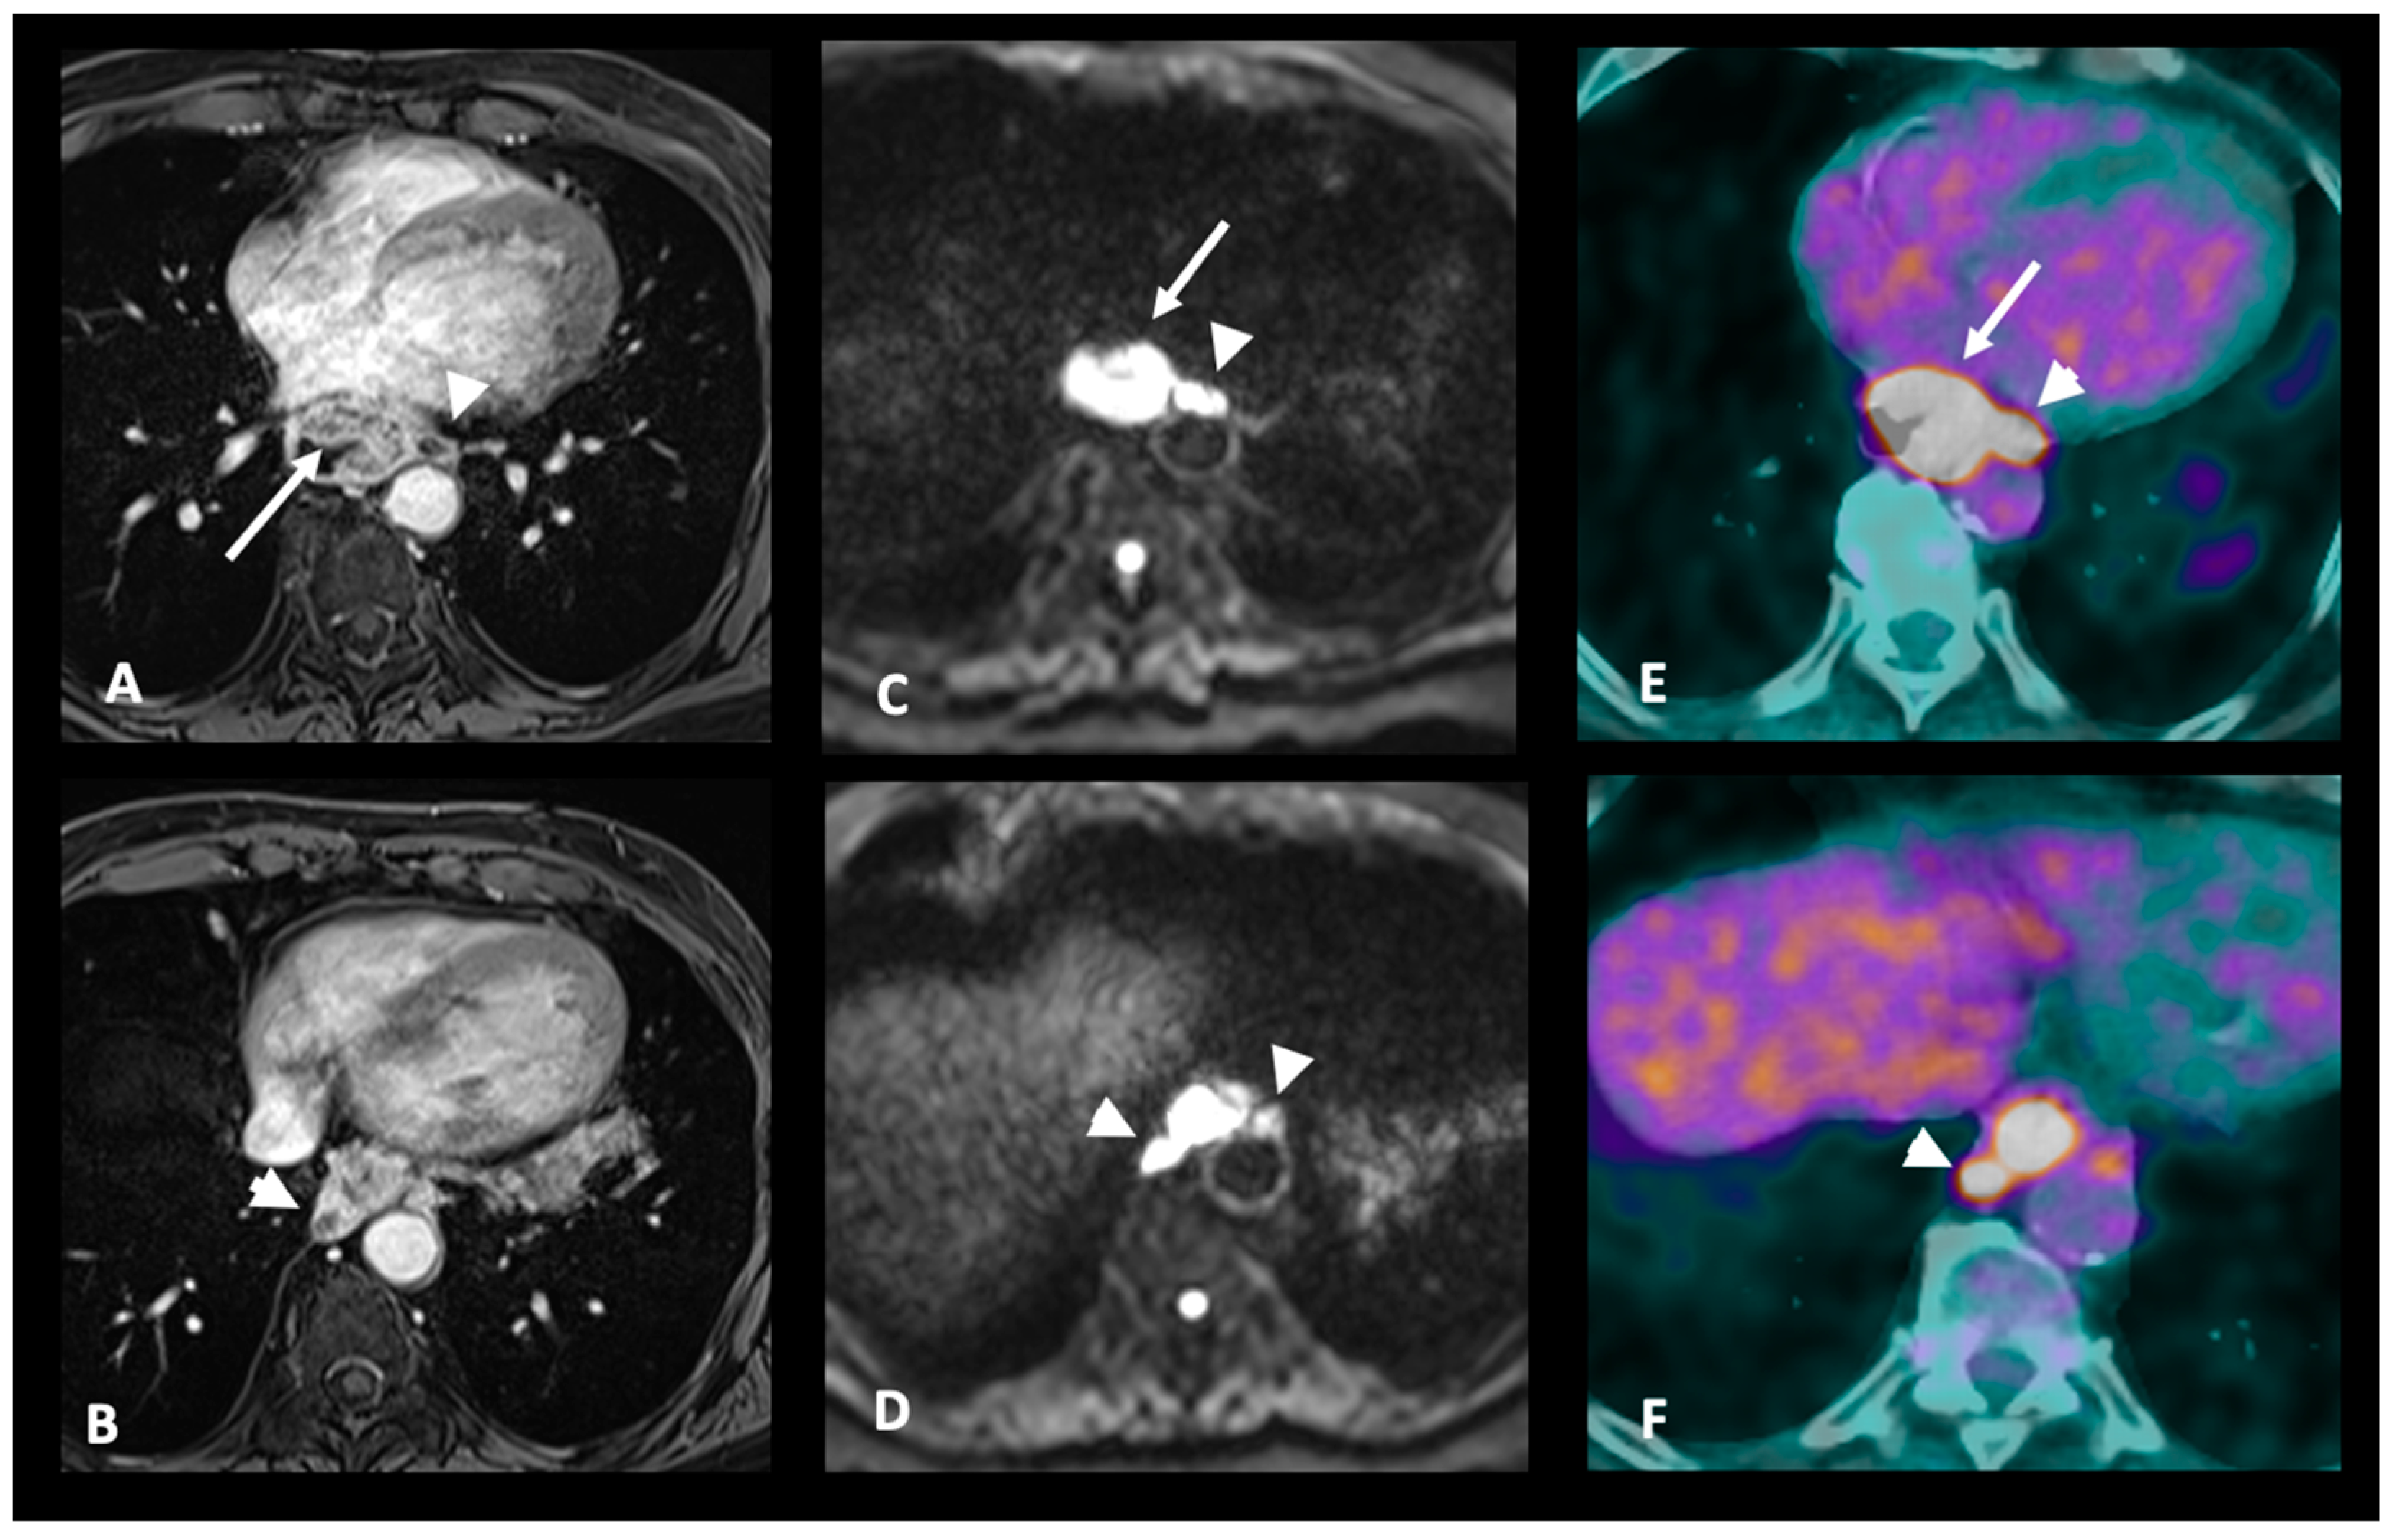

3.3. M Staging

| M+: Distant metastases | MRI-M+: Distant lymph node (sus-clavicular e.g.), liver metastases or other organ metastases |